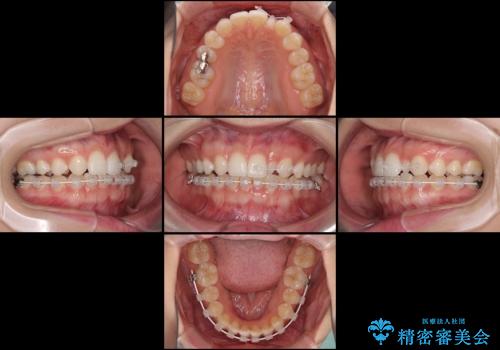

海外転居前に気になる前歯を整えたい 上下前歯の部分矯正

- 1年後に海外に転居するため、気になる前歯を矯正治療で整えたいとのことで来院された患者様です。

下顎は叢生が強かったため、奥歯までワイヤーを装着し、上顎は前歯の一部のみ気になっていたので、その部分にだけワイヤー装置を装着することとしました。